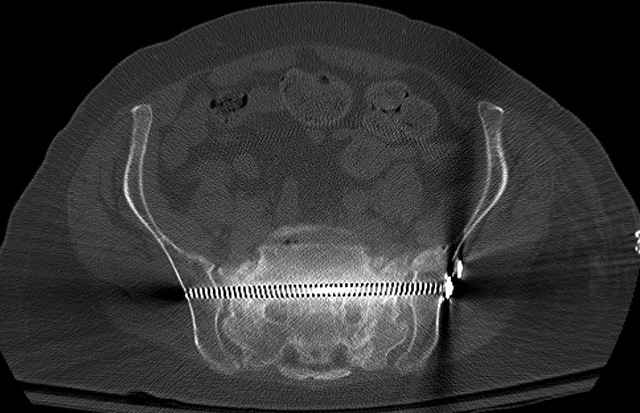

Pelvic CT Scan - 3 Months After Fall

Sacral Injuries

Ramus Fractures

Percutaneous Fixation